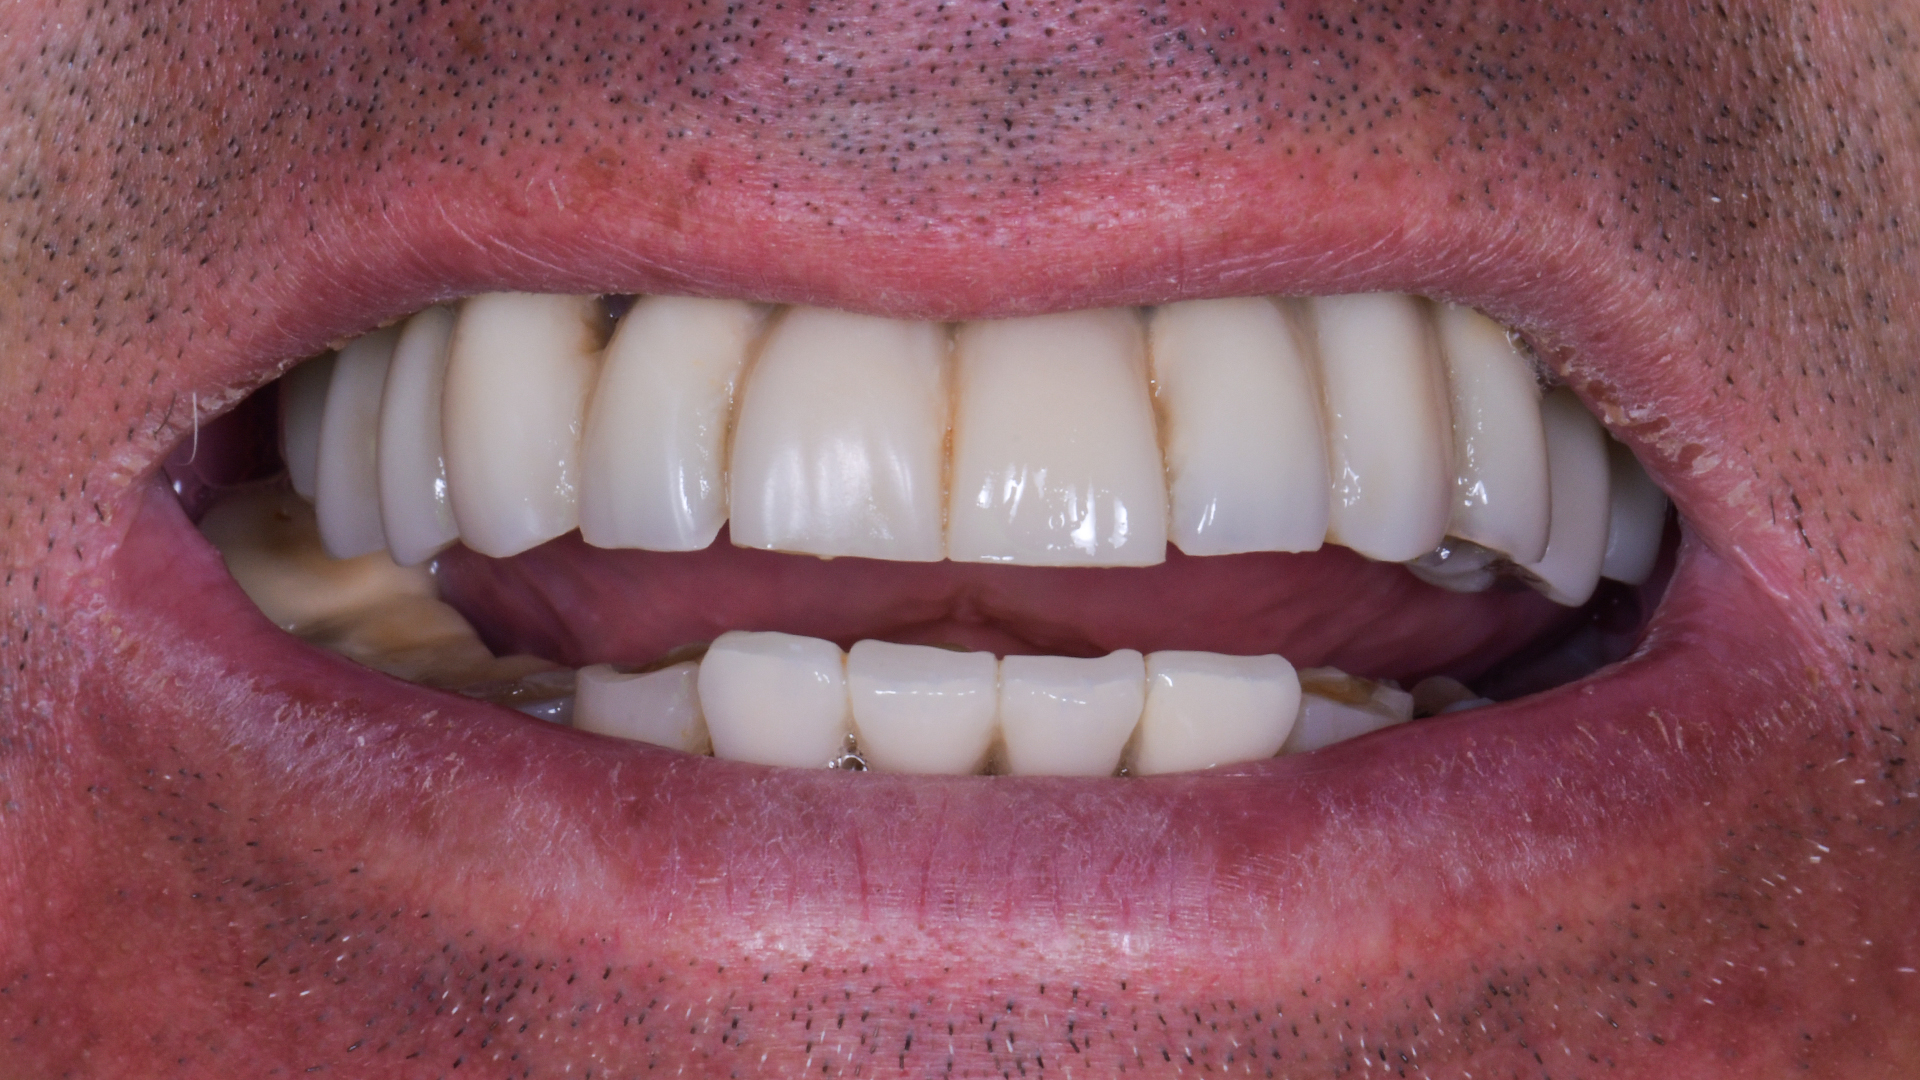

La situazione protesica precedente è questa e ti prometto che a breve pubblicherò anche la soluzione protesica del caso.

Ma per ora vediamo come ho messo questi impianti.